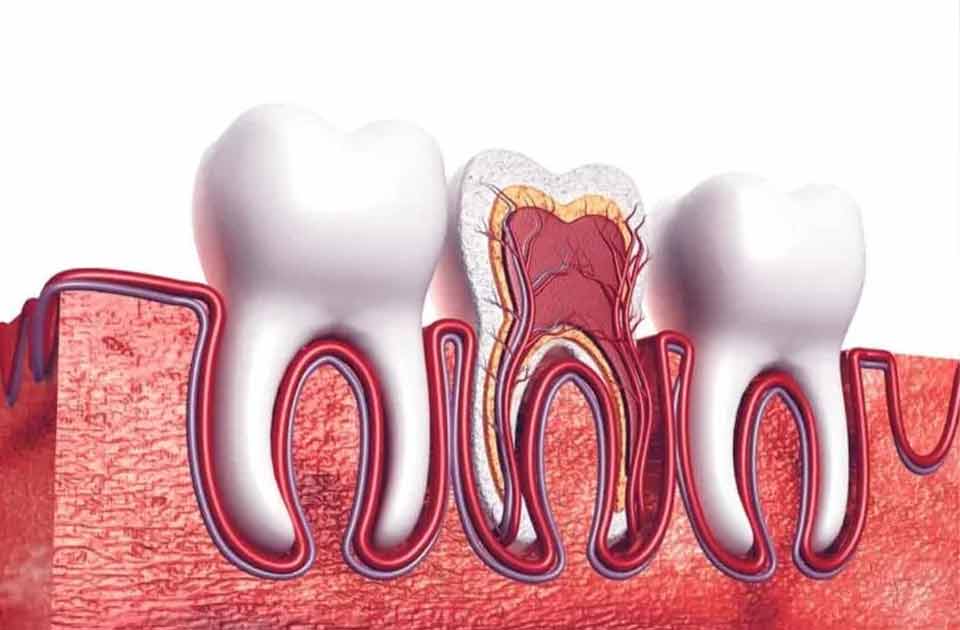

درمان ریشه دندان چیست ؟

درمان ریشه دندان شامل تمیز کردن ناحیه پالپ عفونی یا ملتهب دندان است . درمان کانال های ریشه می توانند دندان ها را نجات بدهند و عملکرد آن را بازیابی کنند به طور معمول ، پس از کامل شدن کانال ریشه ، ناحیه مهر و موم می شود تا از ورود باکتری های آینده به منطقه جلوگیری بشود .